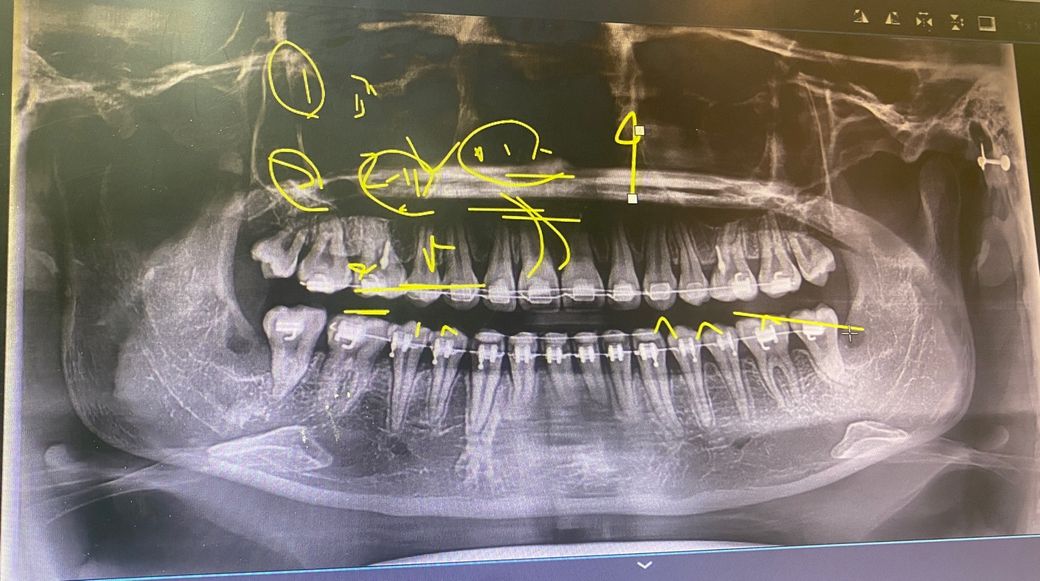

턱관절 증상, 엑스레이 문제 있나요?

안녕하세요. 턱관절 관련 증상을 겪은지 2년 정도 됐습니다.

턱관절이 뒤로 밀린건지, 관절 내 공간이 좁은지, 뼈가 갈렸는지, 턱관절 모양 자체가 불리하다던지 등등.. 문제가 있을까요

제가 보기엔 오른쪽 관절 내 공간이 더 좁고, 하악도 오른쪽이 더 뒤로 들어가있는건 맞는 것 같거든요..

과두 모양도 오른쪽이 더 얇아진 것 같은데 ..

이런 증상들을 미루어 보아 뭐라고 진단을 하실 것 같나요? 정말 턱관절 자체에는 문제 없어보이실까요

방사진 사진상에서는 초점의 위치에 따라서 크기가 크거나 작을 수 있습니다. 턱관절 질환의 경우에는 방사선으로 진단을 한다기보다 증상으로서 진단하는 경우가 많습니다.

턱관절에서 소리가 난다면 탁관절 내부에 있는 디스크가 걸린다는 의미이고 통증이 있다면 해당 부위가 과도하게 힘이 가해지고 있는 것입니다. 턱관절 질환의 진행을 방지하기 위해서는 턱관절에 가해지는 힘을 줄이기 위해서 치아를 약하게 닿는 것이 좋습니다.

엑스레이 상으로 보면 턱관절 연골이 많이 닳아잇는것처럼 보입니다. 턱관절이 불편하시면 대학병원 구강내과를 가셔서 턱관절 장치나 물리치료등을 장기적으로 받시는게 좋습니다.